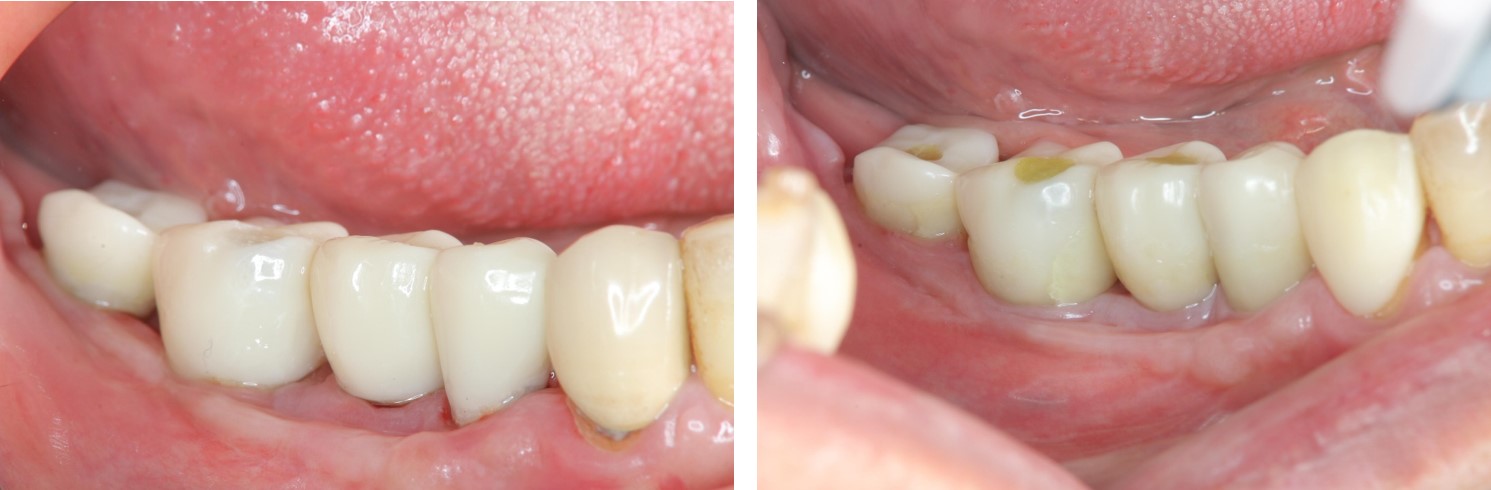

治療後,口內照(終於!我家人的牙齒回來了,雖然看不太習慣,但我家人說她終於找回當年有牙齒的感覺了~果然缺牙還是口腔有問題,找醫生就對了,一般人哪可能自己生出牙齒來!)

自然牙與植牙單顆全瓷冠:#33-37

治療後,口內照